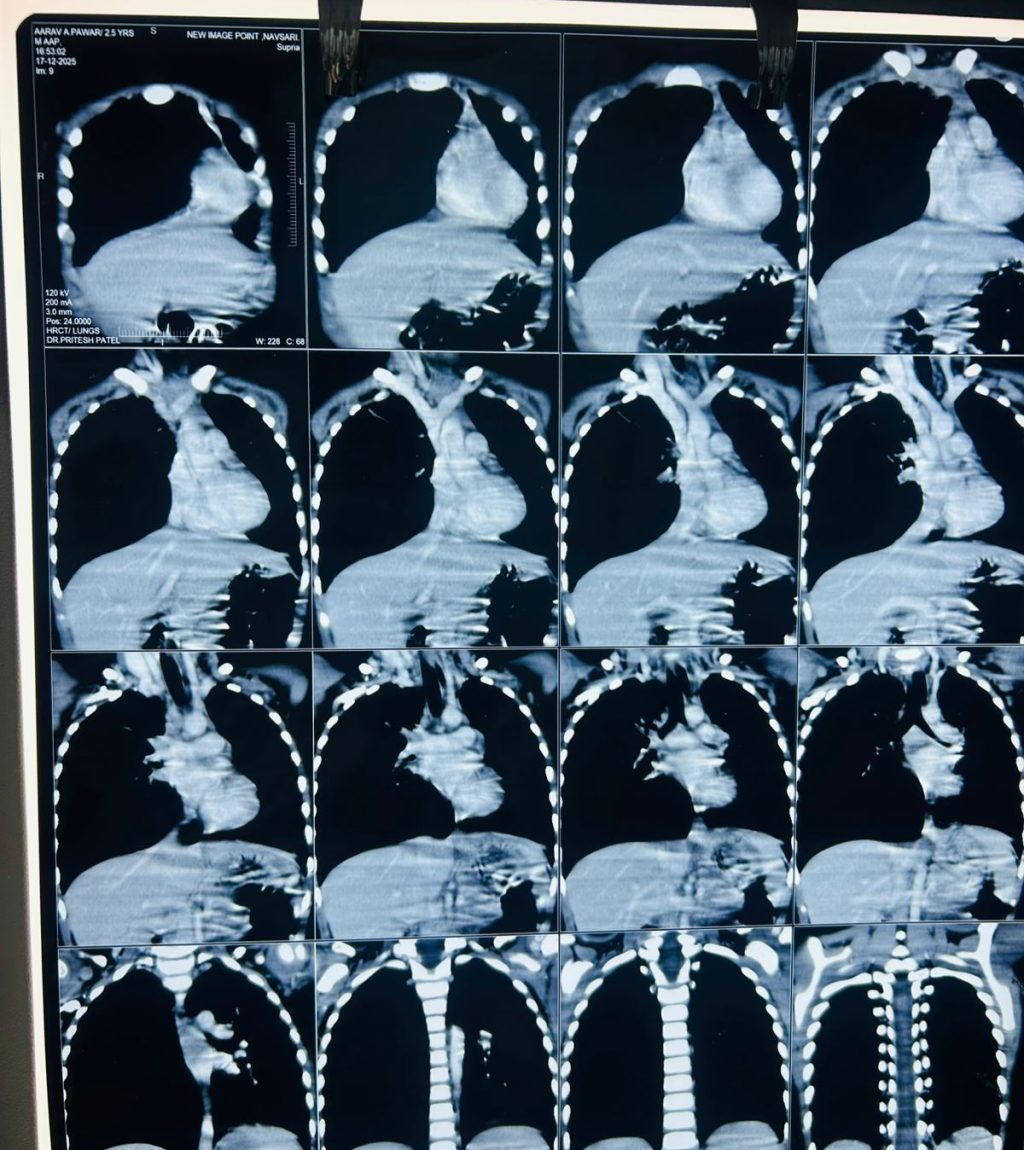

CT SCANNED SUGGESTIVE OF CLE, BRONCHOSCOPY FOUND FOREIGN BODY

(A 2-year-old boy, was admitted because of bad cough, cold ON AND OFF SINCE LAST 1 MONTH AND fever, and fast breathing OF RECENT ORIGIN . On checking, WE found that air was not going properly into his lungs, so he was given WAR oxygen, antibiotics, fluids, and nebulization. Blood tests showed infection. A chest X-ray showed lung infection and swelling of one lung. Since the problem started after eating groundnuts, doctors thought something might be stuck in his breathing pipe. A CT scan was done and showed narrowing of the airway AND  CHANGES OF CONGINITAL LOBAR EMPHYSEMA IN RIGHT SIDE WHICH NEED SURGICAL REMOVAL. So He was sent to a higher hospital FOR SAME, where SURGEON did a bronchoscopy FIRST and found a peanut stuck inside the airway. It was removed, and no surgery was needed. After removal, BABY improved quickly and recovered well.

Key lesson: (Always look at the child’s symptoms and condition, not only test reports.)